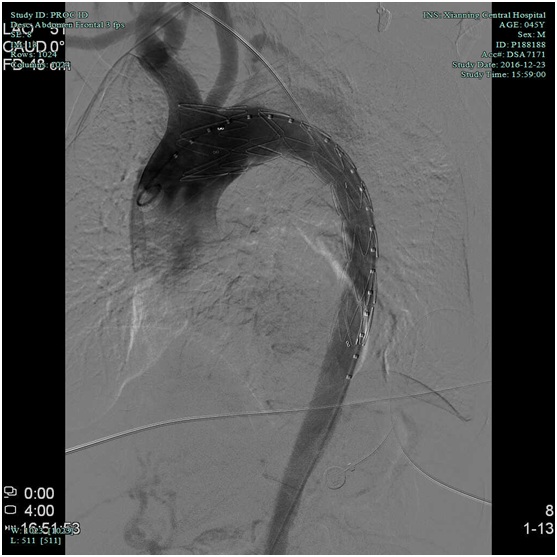

血管外科:胸腹主动脉夹层支架植入术

近日,血管外科在外请专家指导下成功行胸腹主动脉夹层覆膜支架植入术2例,其中一例患者已顺利出院,结束了我院治疗胸腹主动脉夹层需要转院的历史,血管外科将进一步发展血管外科腔内治疗技术和结合手术治疗的血管杂交技术。